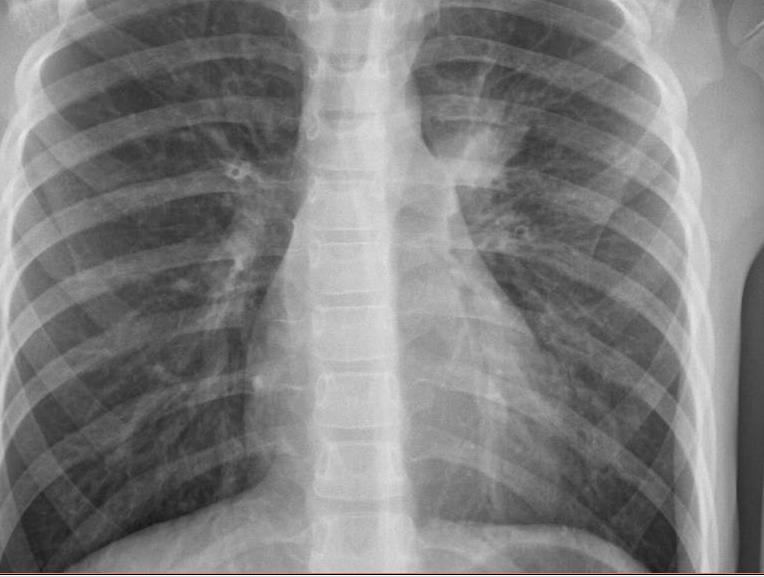

Imaging of Covid 19 infection in children CXR 8 38% 3% 51% 8%

Consolidation 35%

Collapse 3%

PeriBronchial thickening

51%

Hyperexpansion 7%

Effusion 4%

Imaging of Covid 19 infection in children CXR 9 C O V I D

Birmingham

Covid 19 CXR Imaging of Covid 19 infection in children